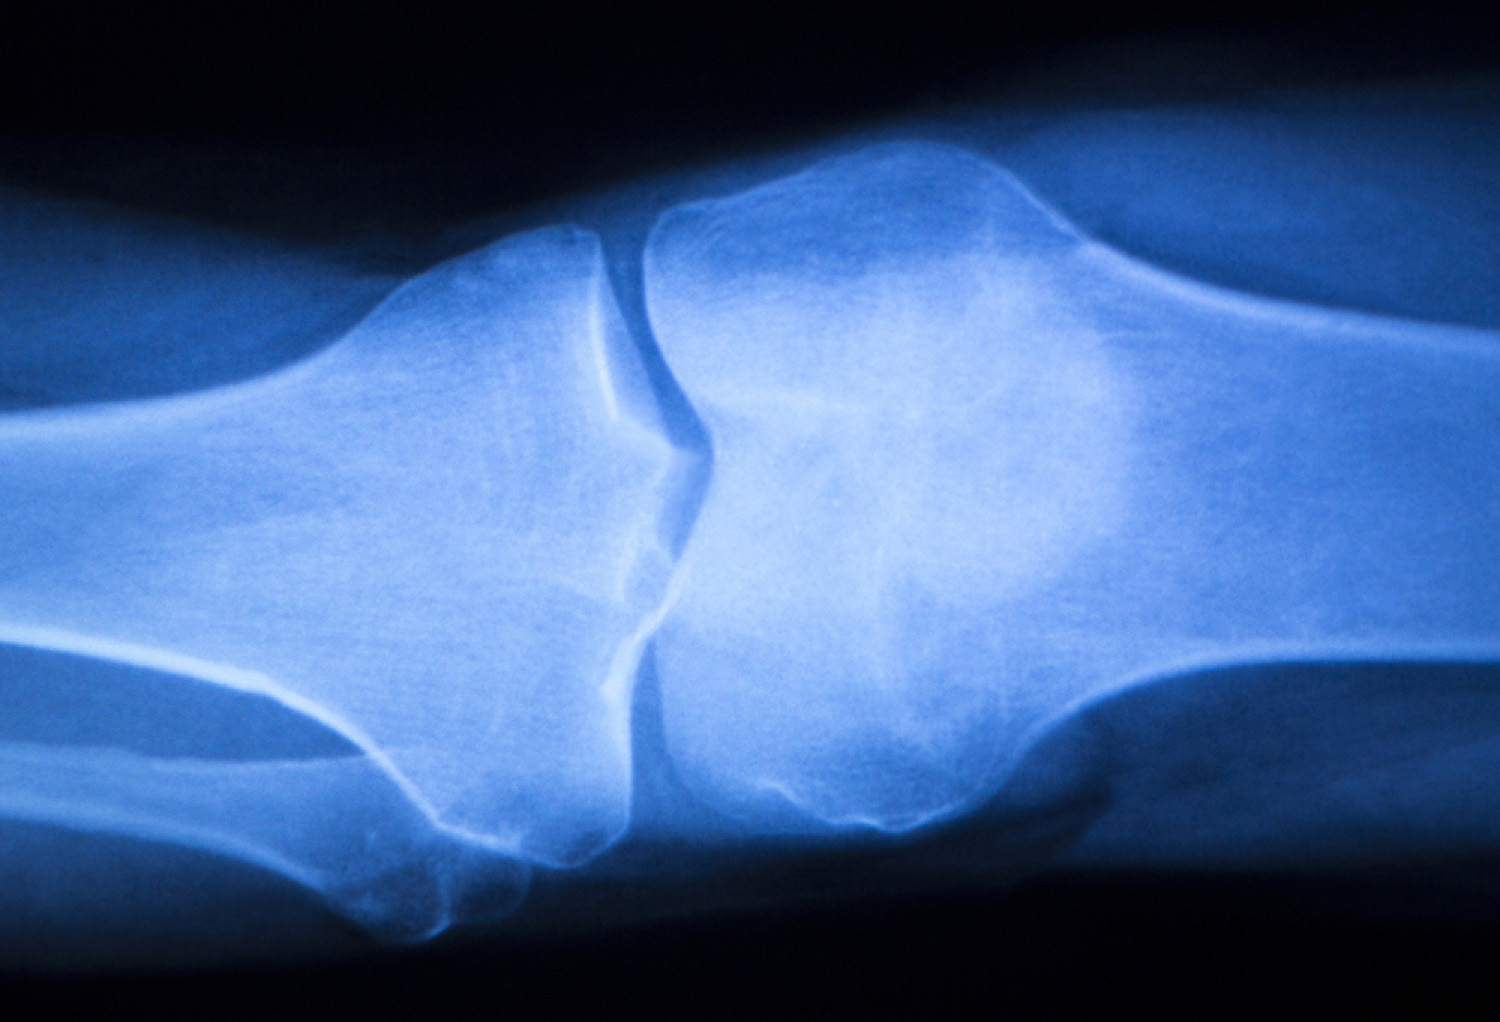

Imaging

Plain film X-rays are often unnecessary unless the clinician would like to appraise the degree of gapping of the medial joint line under imaging. In 1 study, a load applied by a clinician into a knee with a simulated isolated tier III s-MCL injury increased medial joint gapping, compared with that in the intact knee, by 1.7 and 3.2mm at 0 and 20 degrees of flexion, respectively(45). A complete lateral knee trauma, with sectioning of this s-MCL and d-MCL and the anterior oblique ligament, increased gapping by 6.5 and 9.8mm at 0 and 20 degrees of flexion respectively, below the clinician-applied load (45).Magnetic resonance imaging (MRI) is more commonly used to assess the involved structures in patients with injuries to the medial side of the knee (see figure 3). T2-weighted MRI is the gold standard for diagnosing both partial and complete tears of this s-MCL. MRI has an accuracy of 87 percent for the assessment of MCL accidents(46).